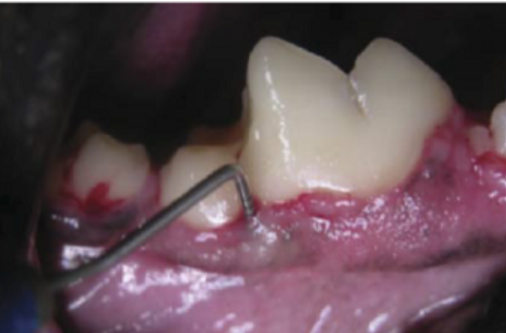

In this lesson, we’ll uncover the latest insights into the etiology and pathogenesis of periodontal disease, explore its far-reaching effects beyond the mouth, and dive into treatment strategies ranging from fundamental care to advanced therapeutic techniques. If you’re looking to refine your approach to dental cases and enhance patient outcomes, this session will provide practical, evidence-based guidance you can apply immediately in practice.

1. Uncover the root cause of periodontal disease and its progression.

2. Recognize the systemic and local impacts of untreated periodontal disease.

3. Master treatment strategies from routine prophylaxis to advanced periodontal therapy.